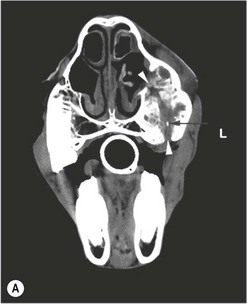

image image image

Fig. 13.43 Radiograph (A) and CT images (B and C) of a compound odontoma in a 2-year-old TB colt.

(Images courtesy of J. Easley.)